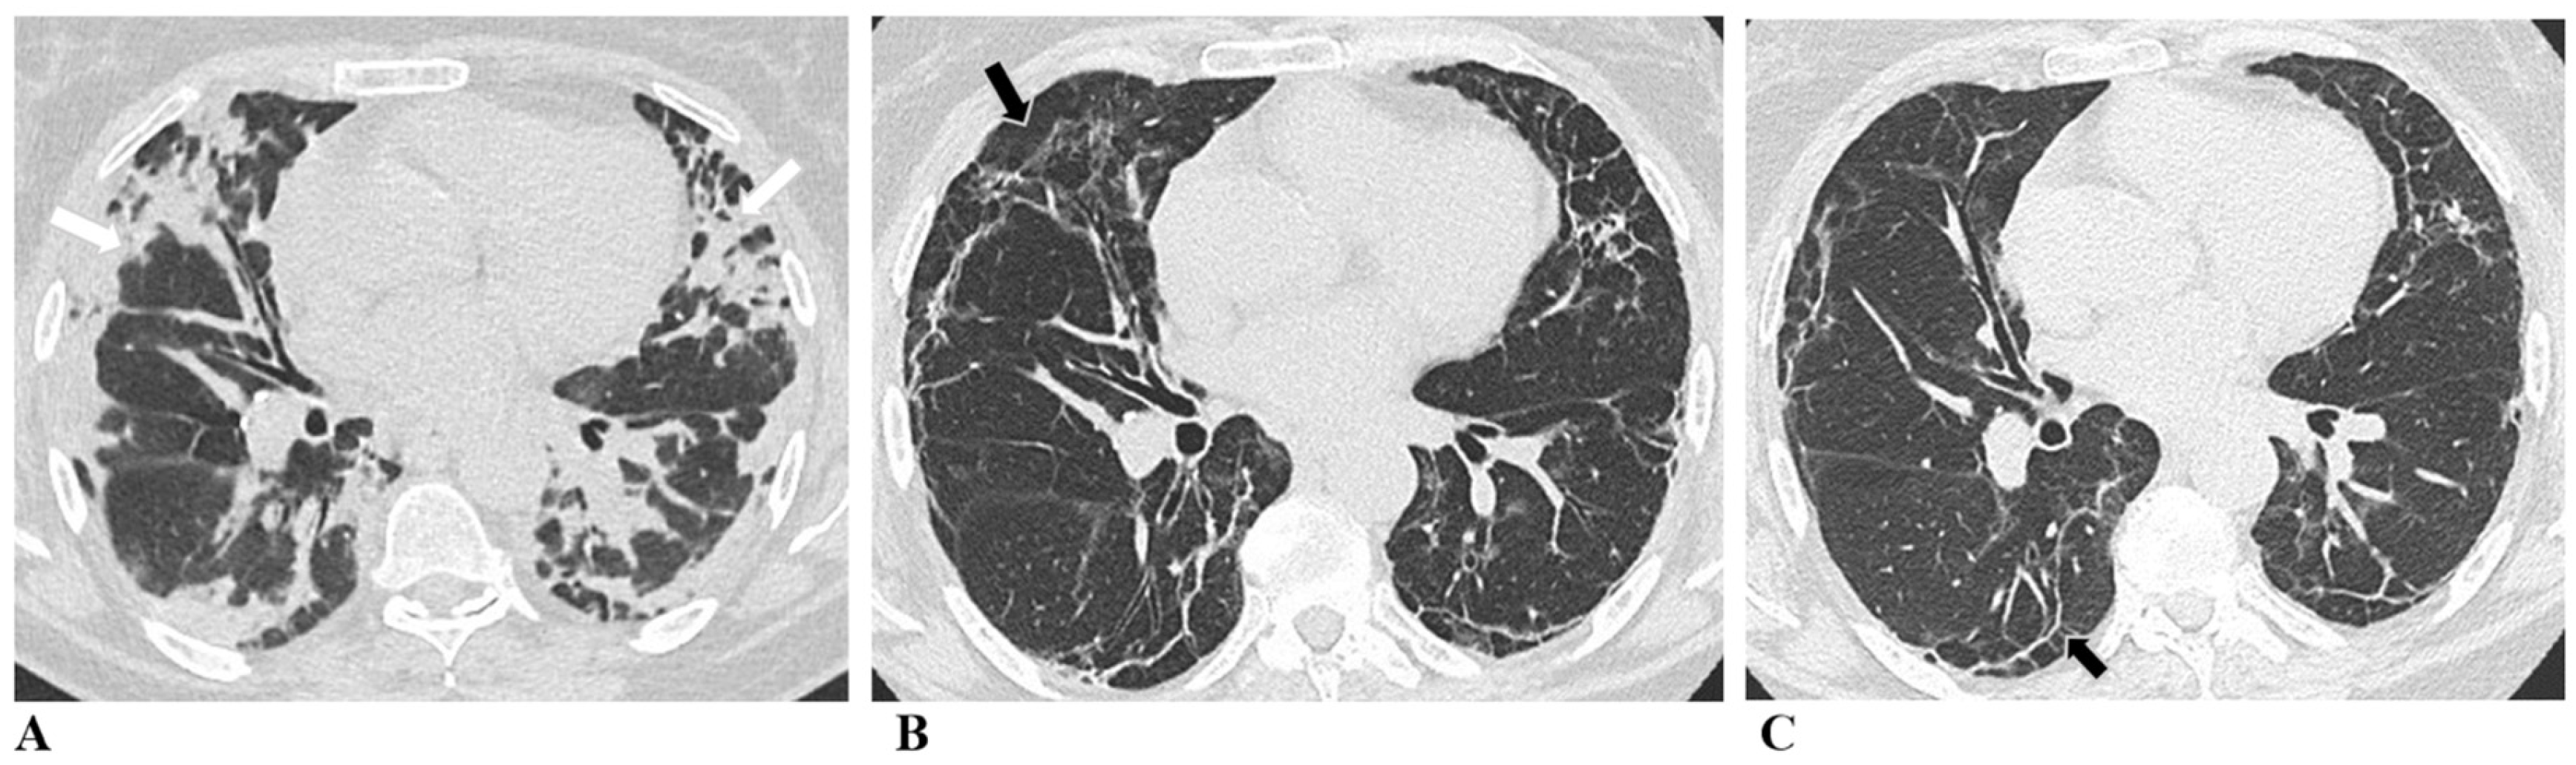

The representative radiological changes over time are shown in

Figure 2.

A total of 76 out of 85 patients returned for the 6-month CT evaluation, and 79 returned for the 12-month radiological evaluation. Fibrotic/reticular changes were assessed in 78 of these patients. A total of 77.63% of patients still had residual inflammatory changes on CT at 6 months after the discharge. The lower lobes of the lungs were predominantly affected: the right lower lobe (RLL) in 73.68% of patients and the left lower lobe (LLL) in 69.74%. Additionally, inflammatory changes were observed in the right upper lobe (RUL) in 64.47% of patients, the left upper lobe (LUL) in 64.47%, and the right middle lobe (RML) in 53.95%. The total CT inflammatory change severity score was 8 (IQR 1–14).

A total of 69.62% of patients had residual inflammatory changes on CT at 12 months post-COVID-19. The RLL was affected in 64.56% of patients, the RML in 48.10%, the RUL in 53.16%, the LLL in 60.76%, and the LUL in 54.43%. The total CT inflammatory change severity score at 12 months was 6 (IQR 0–12), which was statistically significantly lower compared to the 6-month CT inflammatory change severity score (p < 0.001).

A total of 82.89% of patients had fibrotic/reticular changes on CT at 6 months post-discharge. The lower lobes of the lungs were mainly affected: RLL in 75% of patients and LLL in 69.74%. The RUL was affected in 64.47% of patients, the LUL in 69.74%, and the RML in 53.95%. The total CT fibrotic/reticular change severity score was 6 (IQR 2–11).

A total of 73.08% of patients had fibrotic/reticular changes on CT at 12 months post-COVID-19. The RLL was affected in 66.67% of patients, the RML in 51.28%, the RUL in 51.28%, the LLL in 61.54%, and the LUL in 56.41%. The total CT fibrotic/reticular change severity score at 12 months was 4.5 (IQR 0–10), which was statistically significantly lower compared to the 6-month CT inflammatory change severity score (p < 0.001).